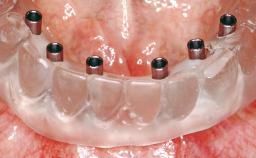

A 35-year-old Caucasian female presenting with advanced periodontal disease involving both the maxillary and the mandibular dentition was referred for evaluation. The patient, a non-smoker in good general health, requested treatment for recurrent periodontal abscesses, tooth mobility, and discomfort during chewing, as well as restoration of her missing teeth with a fixed prosthesis to improve mastication and esthetics. All residual maxillary teeth exhibited plaque deposits, deep pockets, bleeding on probing, and class III mobility and were evaluated as hopeless. All residual mandibular teeth except tooth 37 could be maintained after periodontal therapy.

# of Implants 8

Loading Protocol Conventional or early